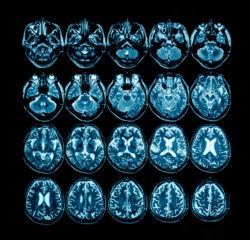

Multiple Sclerosis Drug Zinbryta Linked to Inflammatory Brain DisordersThe multiple sclerosis drug Zinbryta has been voluntarily recalled from the worldwide market due to reports of encephalitis and meningoencephalitis.

Encephalitis is a very serious life-threatening condition pertaining to the inflammation of brain tissue. While it is most often caused by a viral infection, bacterial infection, or immune system disorder, it’s also been linked as a side effect of Zinbryta. While some signs of the condition are flu-like, other symptoms may include some of the following: